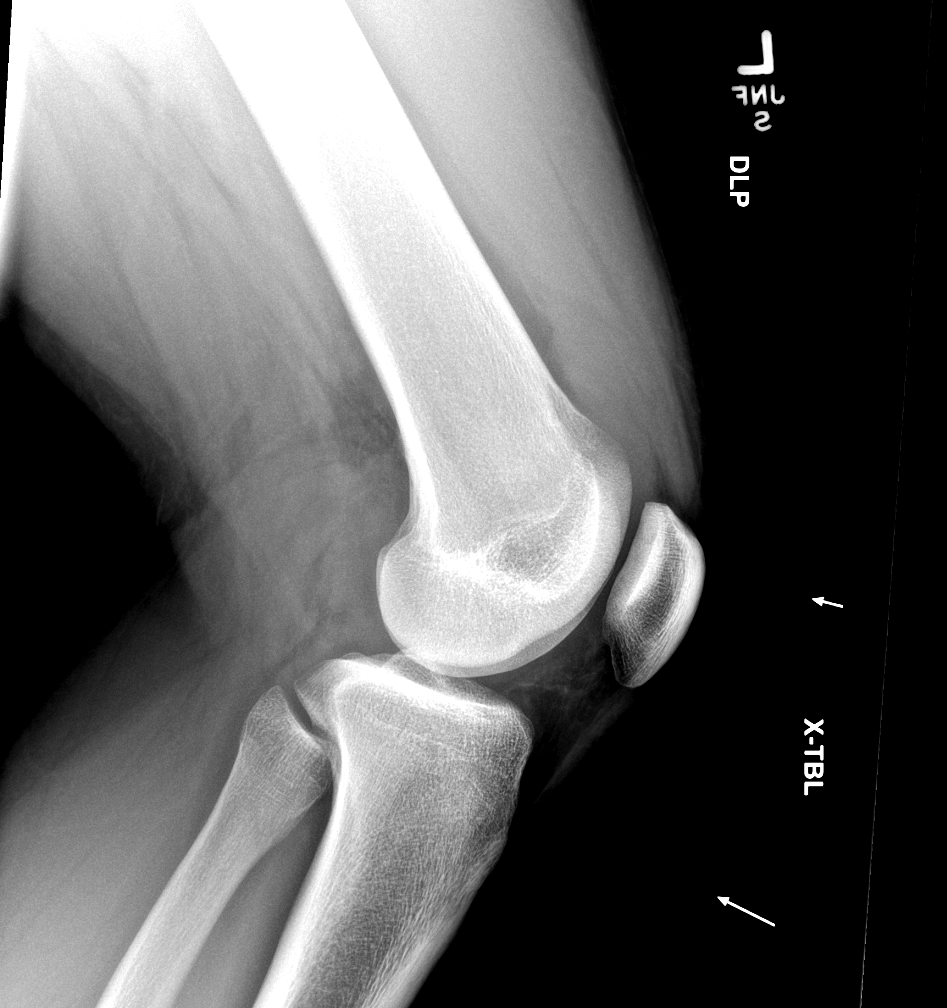

Findings

Bone

Growth plates, ossification centers, apophyses

Joints and alignment